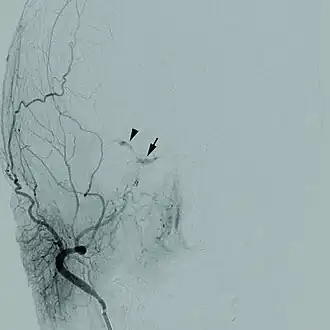

Sur les veines cérébrales peuvent survenir des affections neuro vasculaires telles que la thrombophlébite cérébrale qui correspond à une thrombose d’une veine cérébrale due à la présence d’une tumeur ou un hématome la comprimant.

Sur ces vaisseaux peuvent survenir des pathologies neuro-vasculaires tels que les ischémies (thrombose et embolie), la partie de l’organisme qui se situe après l’obstruction n’étant plus vascularisée cela va donc entraîner une perte de fonction cérébrale, ainsi que les hémorragies dues à l’hypertension artérielle ou encore à une malformation des artères.